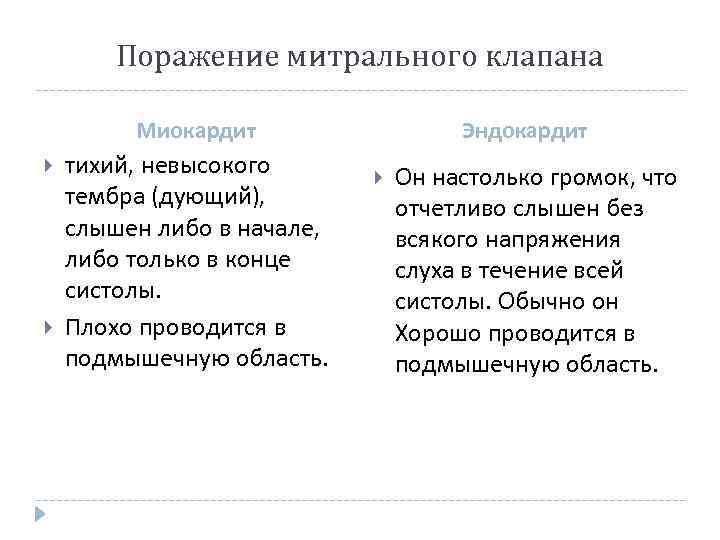

Поражение митрального клапана Миокардит тихий, невысокого тембра (дующий), слышен либо в начале, либо только в конце систолы. Плохо проводится в подмышечную область. Эндокардит Он настолько громок, что отчетливо слышен без всякого напряжения слуха в течение всей систолы. Обычно он Хорошо проводится в подмышечную область.

Поражение митрального клапана Миокардит тихий, невысокого тембра (дующий), слышен либо в начале, либо только в конце систолы. Плохо проводится в подмышечную область. Эндокардит Он настолько громок, что отчетливо слышен без всякого напряжения слуха в течение всей систолы. Обычно он Хорошо проводится в подмышечную область.